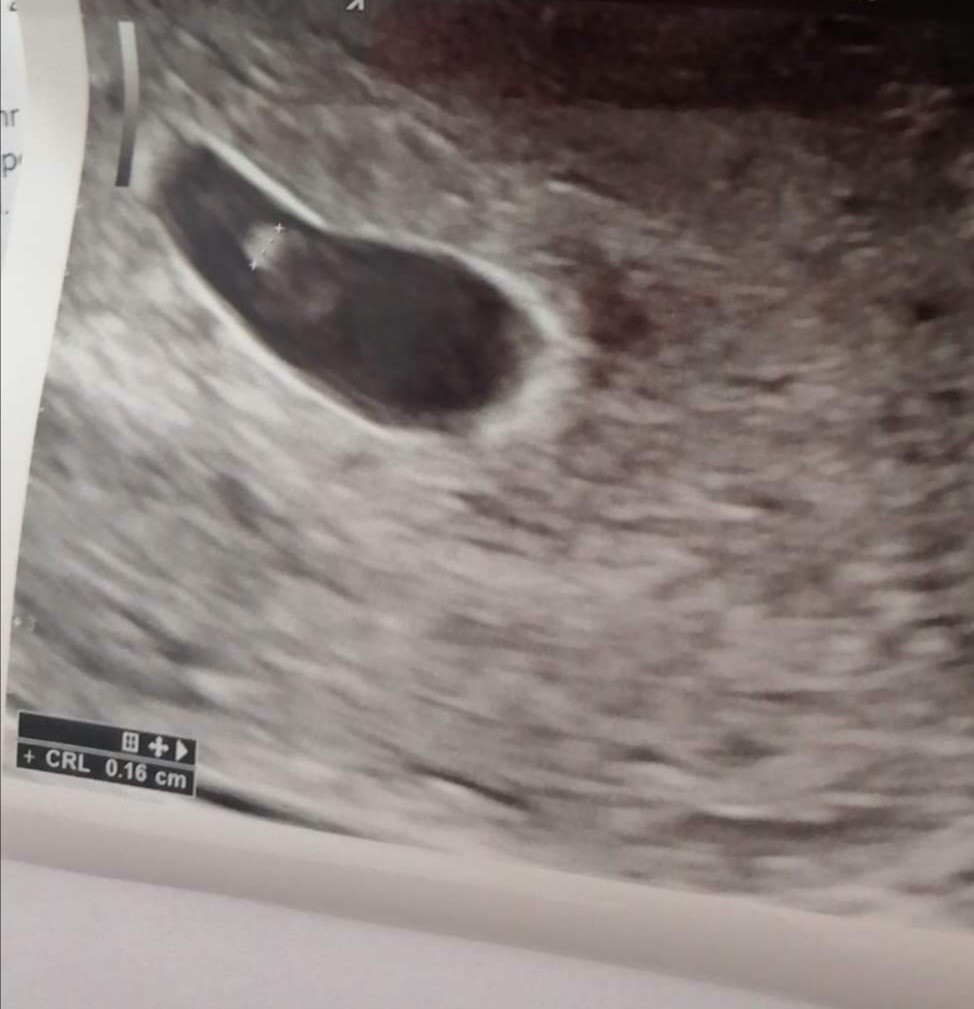

u mnie ciąża potwierdzona betą w 34 dc - 442, po 72 godzinach - 1430 no i oczywiście usg w dn. 5+3,ktorego zdjęcie załączam.. Kolejne usg 27.05 i jestem już przerażona... trzymam za Was wszystkie kciuki i pozdrawiam serdecznie!!! [emoji5][emoji5]